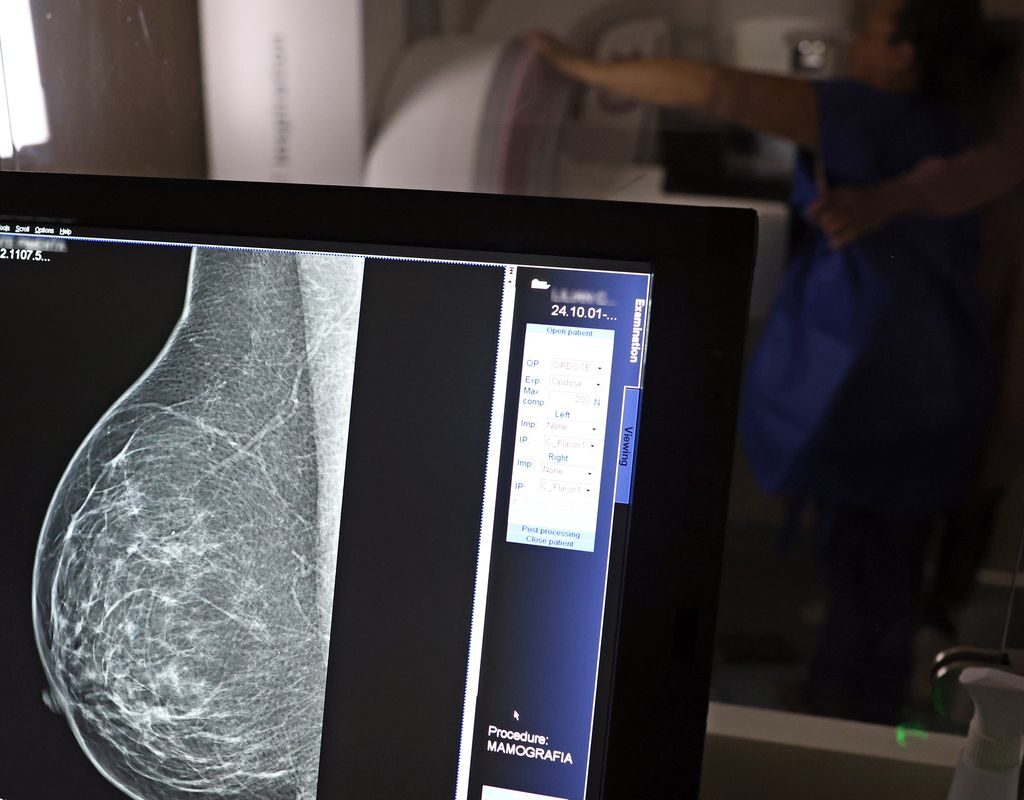

O direito já estava incluído na CLT desde 2018. A partir de agora, as empresas passam a ser obrigadas a divulgar essa informação, além de outras relacionadas a campanhas oficiais de vacinação contra o HPV e sobre o acesso a serviços de diagnósticos de cânceres de mama, próstata e de colo do útero.

O texto estende o uso das folgas também para a realização de exames preventivos do HPV, além dos de câncer que já estavam previstos na legislação anterior. A a Lei 15.377 foi sancionada pelo presidente Luiz Inácio Lula da Silva, e publicada na edição do Diário Oficial da União (DOU).